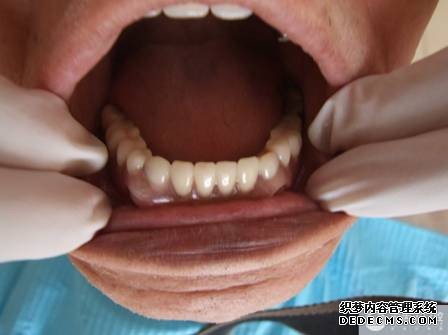

取牙颌模型    义齿加工成型 义齿加工成型    戴入口内 戴入口内    修复完成 修复完成